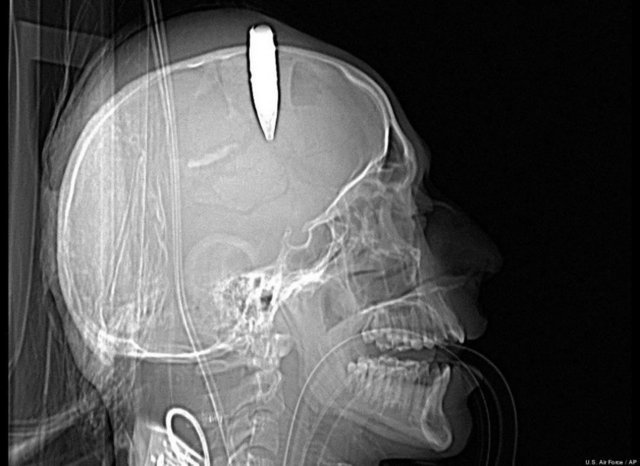

"Özellikle havaalanlarındaki girişlerde iki tür cihazı da görebiliriz. Eşyaların geçirildiği X-Ray cihazında X ışınları kullanılarak görüntüleme yapılır. Çantaların içinde ne olduğu X ışınları ile görüntülenir. Burada uygulanan X ışınlarının eşyalara bir zararı yoktur, birikmez, eşyalarda radyasyon kirliliği yapmaz. Bu cihazların çevresi X ışınlarının insanlara zarar vermemesi için kurşun paravanlarla kaplıdır."